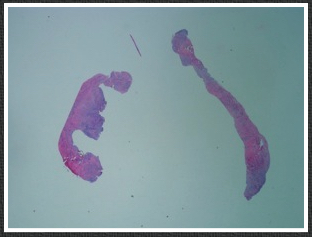

In followup, he developed at worsening stenosis in the distal graft at around 10 months post-op. Arteriography showed a moderate stenosis due to a valve that appeared to close. It was reported retained valve cusps which was strange because the vein was reversed. The flow was noted to be sluggish in the distal runoff, without a distal anastomotic stenosis. He was taken to the operating room, and this valve station was exposed and it had a severe stenosis due to valvular hypertrophy. This was repaired with patch angioplasty. At that time, I thought that this had developed due to a dynamic stenosis. No other stenoses were seen at that time.

In followup, after an initial period of two months without symptoms, the patient developed claudication that worsened. Graft duplex showed a severe stenosis in the mid graft. This was a valve station that was proximal to the previously treated valve station.

I took him to the operative endovascular suite, and arteriography showed a severe stenosis (image above, right) due to a hypertrophied valve. .